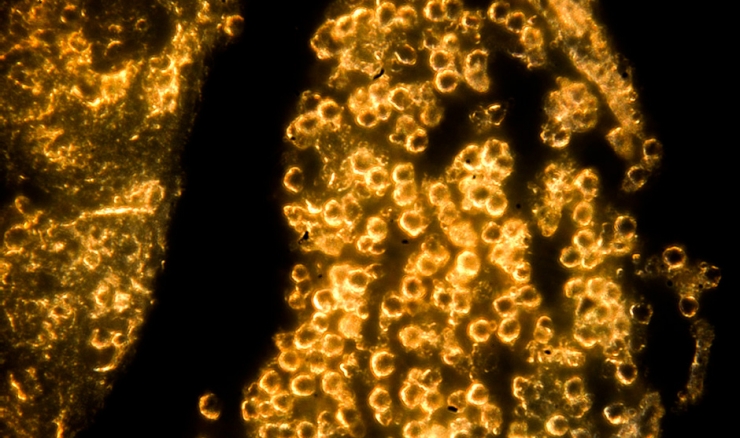

Cientistas conseguiram fazer esferas de ouro muito pequenas e as cobriram com medicamentos usados na quimioterapia.

Quando as minúsculas partículas foram inseridas no centro das células do tumor, estas células pararam de se replicar e muitas delas morreram.

Mas, agora, os pesquisadores de Cambridge criaram nanoesferas – partículas que são 4 milhões de vezes menores do que um fio de cabelo humano cortado na transversal.

No centro destas nanoesferas, estão partículas minúsculas de ouro, cercadas de camadas de cisplatina, um remédio usado em quimioterapia.

Os cientistas testaram as nanoesferas em amostras de tumores no cérebro extraídas de pacientes durante cirurgias.

Em testes realizados nestas amostras de tumores humanos, as esferas pareciam aumentar a eficácia da radioterapia e da quimioterapia tradicionais, melhorando as chances de todas as células do tumor serem exterminadas.